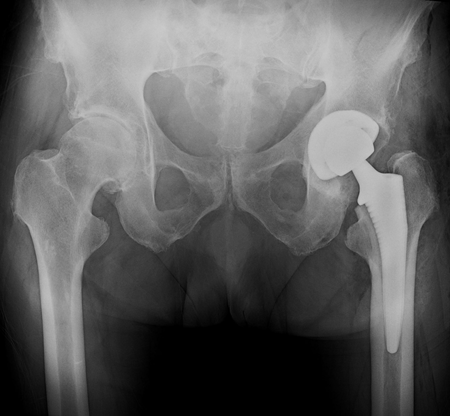

人工全髋关节置换术后x线片

人工髋关节置换是各种髋关节终末期疾病的有效治疗方法。髋关节假体的寿命与膝关节类似,受到多种因素的影响,包括患者的年龄、活动量、体重、感染/骨折等并发症,以及假体的摩擦界面选择、固定方式等。髋关节置换的15年生存率在年轻患者(<65岁)已达80%,在老年患者(>65岁)高达94%。

与膝关节相比,髋关节假体的摩擦界面、固定类型可选择的种类更多。髋关节置换在近40年经历了很多革命性的进展,患者术后的活动度、假体寿命等都得到大幅提高。在上世纪70~80年代,髋关节置换的主流是水泥固定型假体,其失败原因主要被归结于骨水泥技术的难度较高,以及骨水泥颗粒导致的骨溶解和假体松动。尤其对于年轻、活动量大、肥胖的患者来说,骨水泥固定难以提供满意的远期疗效。这些问题导致了其后髋关节置换向非水泥固定方向发展,尽管水泥固定仍是高龄、骨质疏松患者的最佳选择。然而医生们发现,非水泥固定并不能解决所有的问题,骨溶解成为了导致假体失败的重要原因,甚至固定良好的假体也会存在巨大的骨溶解病灶,这时人们才注意到了聚乙烯磨损与假体松动之间的因果关系。